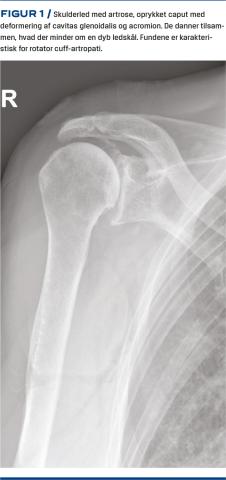

Skulderartrose ses både primært og sekundært i forbindelse med fraktur, ustabilitet eller slid i rotator cuff-senerne. Ved samtidig artrose og rotator cuff-destruktion benævnes tilstanden rotator cuff-artropati (Figur 1). Prævalensen af artrose i skulderleddet er ca. 20% efter 80-årsalderen [1]. Patienter, der opereres med en skulderalloplastik, monitoreres af Dansk Skulderalloplastik Register (DSR) [2]. Her er der påvist en stigning i antallet af alloplastikker, som er indsat pga. artrose eller rotator cuff-artropati, fra 356 i 2008 til 836 i 2019. Årsagen til stigningen er ukendt, men kan skyldes en stigende forekomst af svære tilfælde, bedre behandlingsmuligheder, bedre kendskab til disse eller indikationsskred.